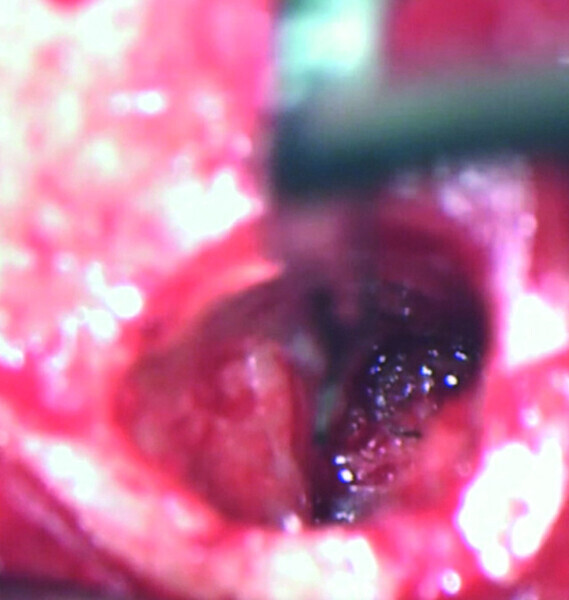

Maxillary sinus and root canal therapy complications